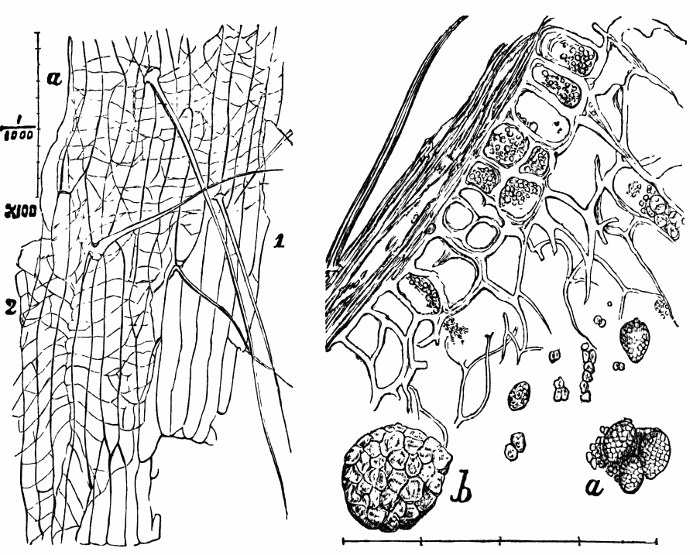

IPECACUAN′HA. Syn. (Ipecacuanha, L.; Ipecacuhan, E., B. P.) Radix ipecacuanhæ, Ipecacuanha (Ph. L. E. & D.), L. The dried root of Cephaëlis Ipecacuanha, or the true ipecacuanha plant, one of the Cinchonaceæ. “Ashy coloured, tortuous, very much cracked, and marked in rings with deep fissures, having an acrid, aromatic, bitterish taste.” (Ph. L.) It occurs in pieces 3 or 4 inches long, and about the size of a writing quill.—Dose. As an emetic, 10 to 20 gr., assisted by the copious use of warm water; as a nauseant, 1 to 3 gr.; as an expectorant and sudorific, 1⁄2 to 1 gr. It is undoubtedly the safest and most useful medicine of its class. It has recently been highly recommended in dyspepsia, combined with other bitters or aperients. Almond meal is sometimes used as an adulterant in ipecacuanha powder.